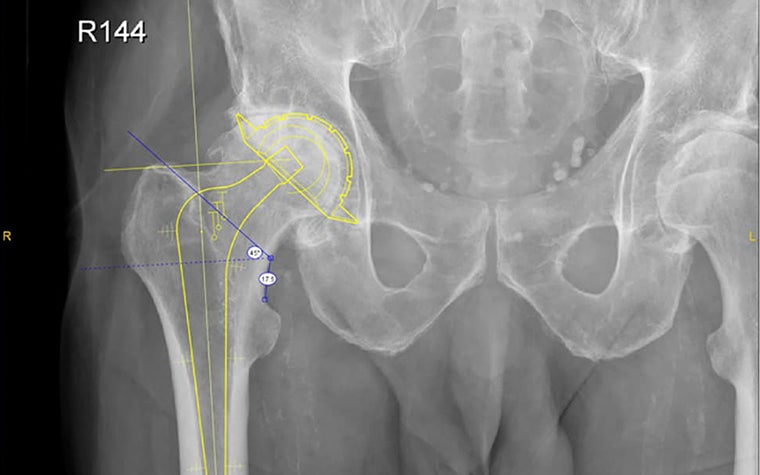

All the x-ray images were templated by Dr. Shaw using Materialise OrthoView Digital Pre-operative Planning Software. The resulting images and reports were saved back to the PACS and a copy of the templated sizes printed on what Dr. Shaw refers to as a “shopping list” or list of prostheses required. This list was used to collect the prostheses most likely to be needed for the surgery that day. In some cases, two optional sizes were recorded when the templating was between two sizes. A clinical decision was then taken at the time of surgery to identify the best option for the patient.

The component sizes recorded were stem size, stem offset, neck length for the 28 mm head, acetabular size and cement restrictor plug size. The neck length and plug sizes were roughly templated and usually two sizes were recorded on the shopping list because Dr. Shaw believes that these component sizes are best judged at the time of surgery.